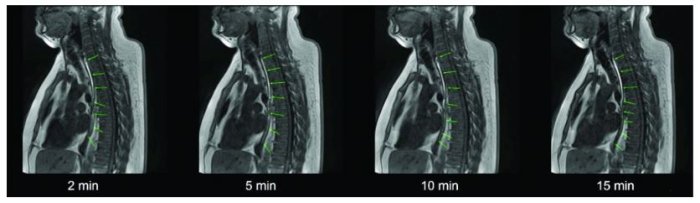

In contrast to tablets, capsules or viscous fluids, which are known for short esophageal transit times, for the first time the EsoCap system ensures a targeted and long-lasting drug delivery in the esophagus. The University of Greifswald team demonstrated, in 12 healthy volunteers, that the EsoCap novel delivery concept, which is based on application of a mucosal adhesive foil, is well accepted and adheres to the esophageal mucosa for at least 15 minutes for maximum treatment efficacy.